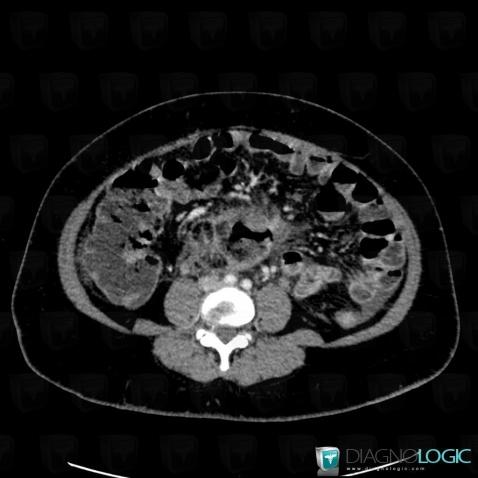

Abscess, Retroperitoneum, CT

Here is the specific information in the key image above:

- Diagnosis Abscess, Location(s) Retroperitoneum, with gamuts